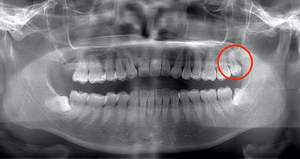

抜くと痛みや腫れが出やすい親知らずとは、横を向いてはえているような親知らずです。こういうケースでは、歯ぐきや親知らずのまわりの骨を削らないといけませんので、どうしても腫れや痛みが伴います。

下顎でこのようなケースは多いですが、上顎でも同じようなケースがあります。

抜くと痛みや腫れが出やすい横向きで生えている親知らず症例のレントゲン写真